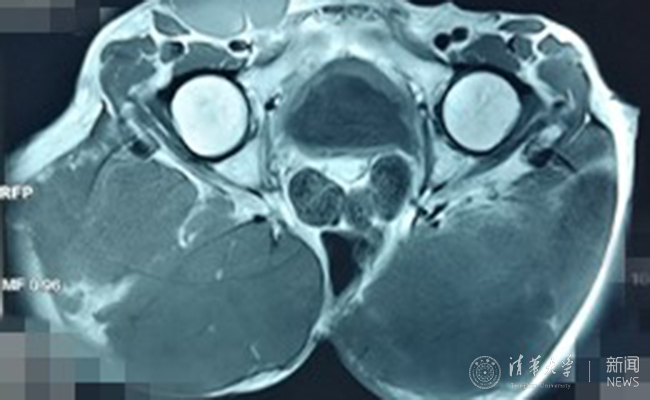

患者的骶骨脊索瘤。

患者术前影像资料。